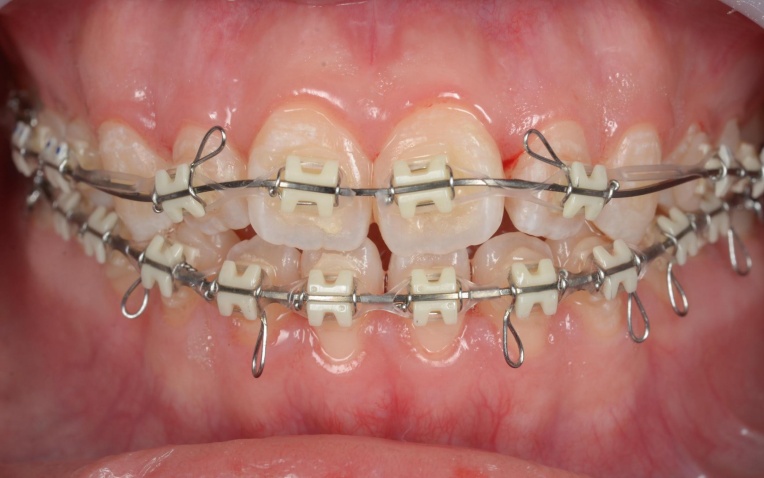

見た目と噛む機能の両方を改善するため、矯正治療を提案し、同意いただきました。 |

18ヶ月 |

| リスク・備考 | ・治療中、発音しにくい場合があります ・治療中、舌が動かしにくいことがあります ・治療中、装置によってまれに頬の内側が傷つき、口内炎になる場合があります ・歯の移動に伴って、違和感や痛みを感じる場合があります ・冷たいものを飲んだときに歯がしみる「知覚過敏」の症状が出る場合があります ・正しいブラッシングやメンテナンスを行わない場合、虫歯や歯周病のリスクが高まります |